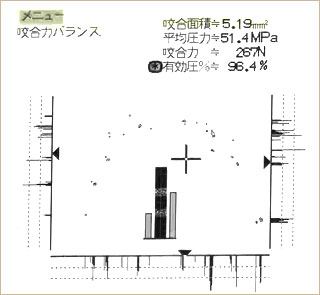

オクルーザーのデータを比較すると、治療前に左の方に偏っていた咬合力が、治療後はバランス良く回復しているのが分かります。